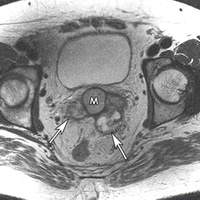

Семинома представляет собой злокачественную опухоль яичка из первичных (зародышевых) половых клеток, присутствующих в организме в период эмбриогенеза.